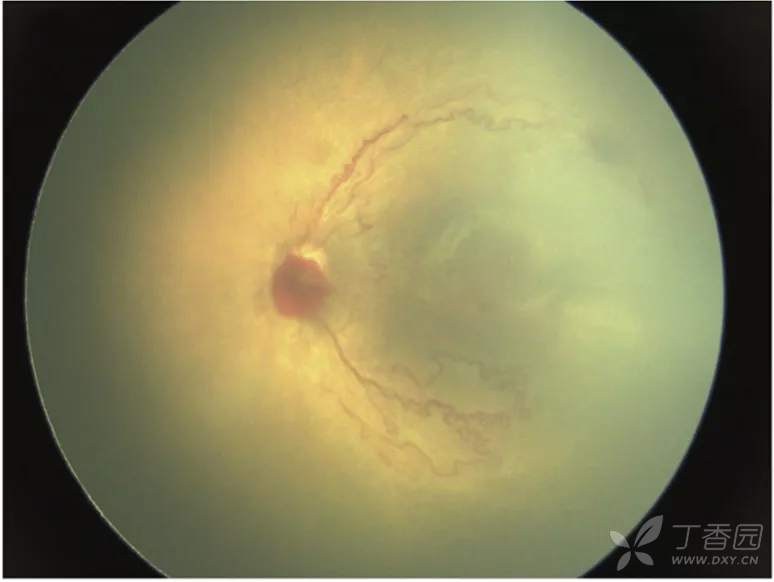

图. 5A期:视网膜完全脱离并可见视盘,提示开放漏斗型脱离。